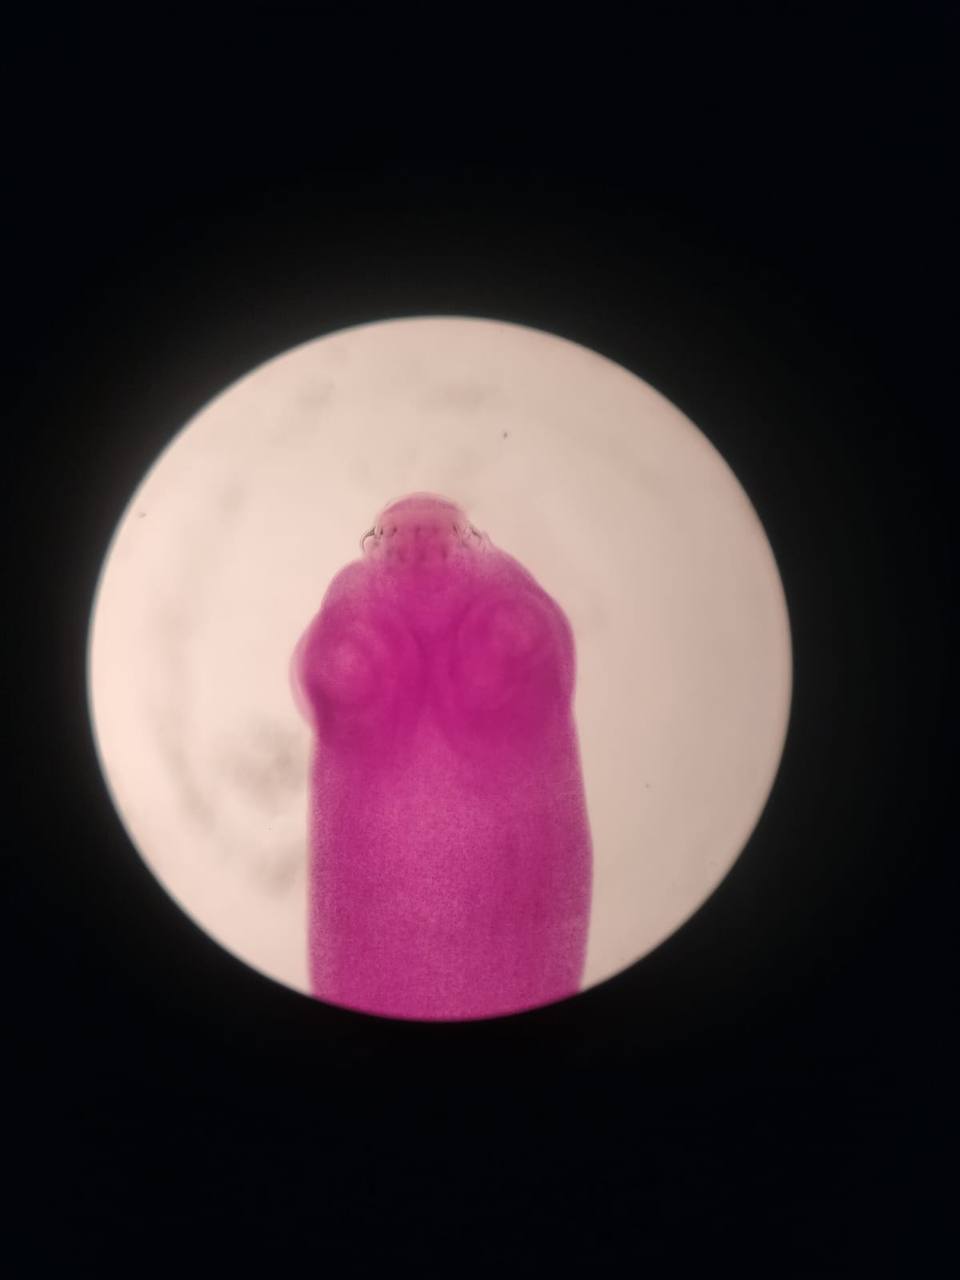

Taenia saginata scolex